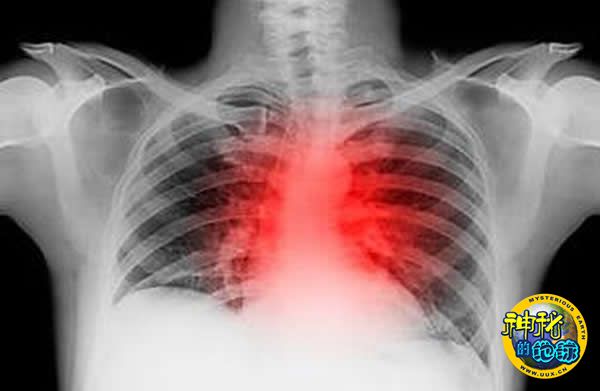

心脏病发作始于血管阻塞,因此,血液检测可以成为预测心脏问题的一种更理想方式。目前,检查心血管状况的最可靠方式就是血管造影。这是一种侵入式方式,需要将一根细细的管子伸入大腿动脉血管。现在,研究人员已经确定了23个为血白质合成指定遗传密码的基因,利用这种方式检查与心脏病有关的血管阻塞情况的准确率高达83%。

如果医生将这种血液检测与现有的心脏病发作风险诊断手段--包括胸疼症状和家族疾病史--结合在一起,确定患者属于高风险还是低风险人群的准确率将比单纯使用传统手段提高16%。期待血检本身能够预测心脏病发作还不切实际,至少目前如此,但对于那些高危患者来说,它可以充当一个早期预警信号。也许通过改变饮食结构和生活习惯,这些患者便可以预防心脏病发作。